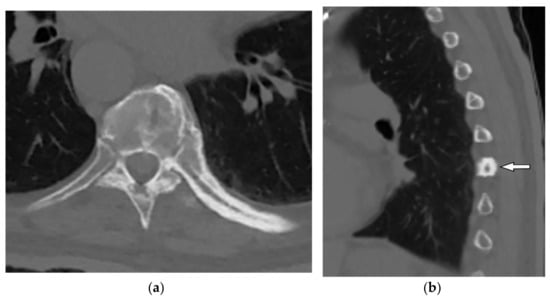

8.2. Tuberculosis Spondylodiskitis

Tuberculosis spondylodiskitis has a more gradual and chronic clinical course, which leads to multi-level involvement and paravertebral cold abscess formation with well-circumscribed thin wall. Subligamentous spread of infection to adjacent vertebral levels, relative preservation of intervertebral disk, and kyphotic angulation (gibbous deformity) are other imaging findings. CT scan is more sensitive in delineating calcification within paravertebral cold abscess, end plate erosion, and bony fragment visualization (Figure 13) [39,42].

Figure 13.

A 65-year-old man with fever, weight loss, and night sweeting. The non-contrast-enhanced CT (bone window) in axial plane (a) shows paraspinal soft tissue mass with erosion of right lateral aspect of adjacent vertebral body. Sagittal T2W image of another patient with the same pathology (b) shows hypersignal intensity within T8-T9 vertebral bodies with also intervertebral disc destruction and narrowing of spinal canal pushing the spinal cord posteriorly. Axial T1WFS + C (c) identified the enhancing paraspinal mass with peripheral rim enhancement (arrow) in its left posteromedial side, which is suggestive of abscess formation. Culture of aspirated pus under guide of CT was compatible with tuberculosis infection.